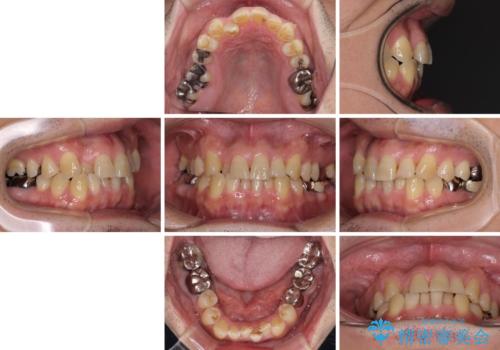

- 近医にてブリッジ治療を行った歯が痛くてたまらないとのことで来院された患者様です。

診察を行ったところ、奥の土台になっている歯は神経組織が失活しており、根尖部に病変があり、そこが原因で痛みを生じている状態でした。

根管治療を行うためにブリッジを除去したところ、むし歯が歯肉の奥深くにあまで及んでいたため、歯周外科処置によりむし歯が歯肉縁より浅い位置へと改善することとしました。

ここまでの治療を提案したところで、折角なのでしっかり治療を行いたいとのことで、前歯のデコボコやクロスバイトを改善するための矯正治療を行うこととしました。

まずは奥歯の痛みを改善し、その後矯正治療を行い、最後にオールセラミックブリッジによる補綴治療を行うこととしました。